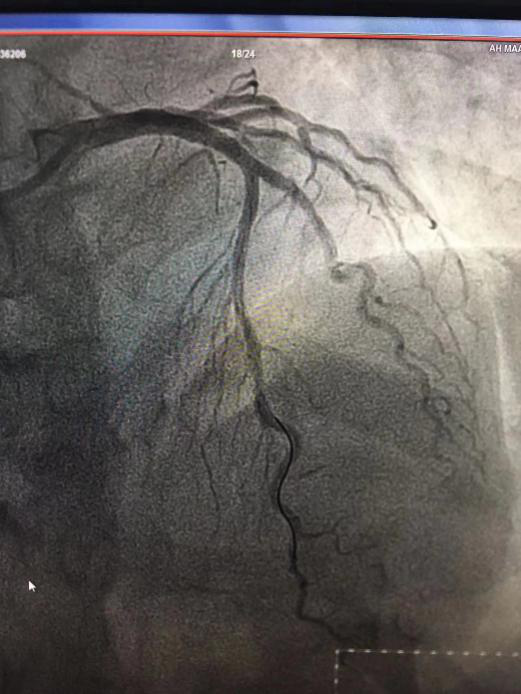

(術(shù)前) (術(shù)后)

時(shí)間就是生命!接診醫(yī)生為患者采集核酸后,胸痛救治團(tuán)隊(duì)立即啟動(dòng)應(yīng)急預(yù)案,在心血管內(nèi)科副主任董學(xué)濱的帶領(lǐng)下,手術(shù)團(tuán)隊(duì)配戴一級(jí)防護(hù)裝備,將患者繞行CCU直接接入導(dǎo)管室實(shí)施手術(shù)。手術(shù)團(tuán)隊(duì)首次經(jīng)歷穿戴防護(hù)服進(jìn)行介入操作,造影結(jié)果提示患者LAD近段80%狹窄、LCX細(xì)小、中遠(yuǎn)段狹窄95%,急診于罪犯血管LCX行球囊擴(kuò)張術(shù),手術(shù)結(jié)束后患者胸痛明顯緩解。介入手術(shù)期間,嚴(yán)密的口罩讓人呼吸困難,沉重的防護(hù)裝備給手術(shù)操作帶來(lái)了巨大的干擾,穿著鉛衣和防護(hù)服讓人汗流浹背,連簡(jiǎn)單的穿刺都變得艱難,但醫(yī)護(hù)團(tuán)隊(duì)齊心協(xié)力、沉著應(yīng)對(duì)、克服困難,最終憑借高超的介入技術(shù)順利化解了危機(jī),挽救了病人的生命!當(dāng)看到擴(kuò)張后的血管血流通暢,患者胸痛癥狀緩解,每個(gè)人的臉上都洋溢著燦爛、開(kāi)心的笑容。一周后,按照心肌梗死病例的救治原則,手術(shù)團(tuán)隊(duì)在患者高度病變的LAD處放入一枚支架。至此,心肌梗死患者的救治全部結(jié)束,目前患者痊愈出院。此次急性心?;颊叩某晒Λ@救,再次彰顯了醫(yī)院胸痛中心的救治能力。